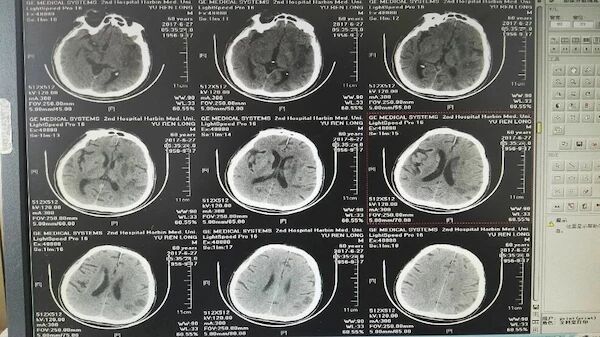

手术前的CT和多模MR

术前脑血管造影显示左侧大脑中动脉急性闭塞,代偿不佳